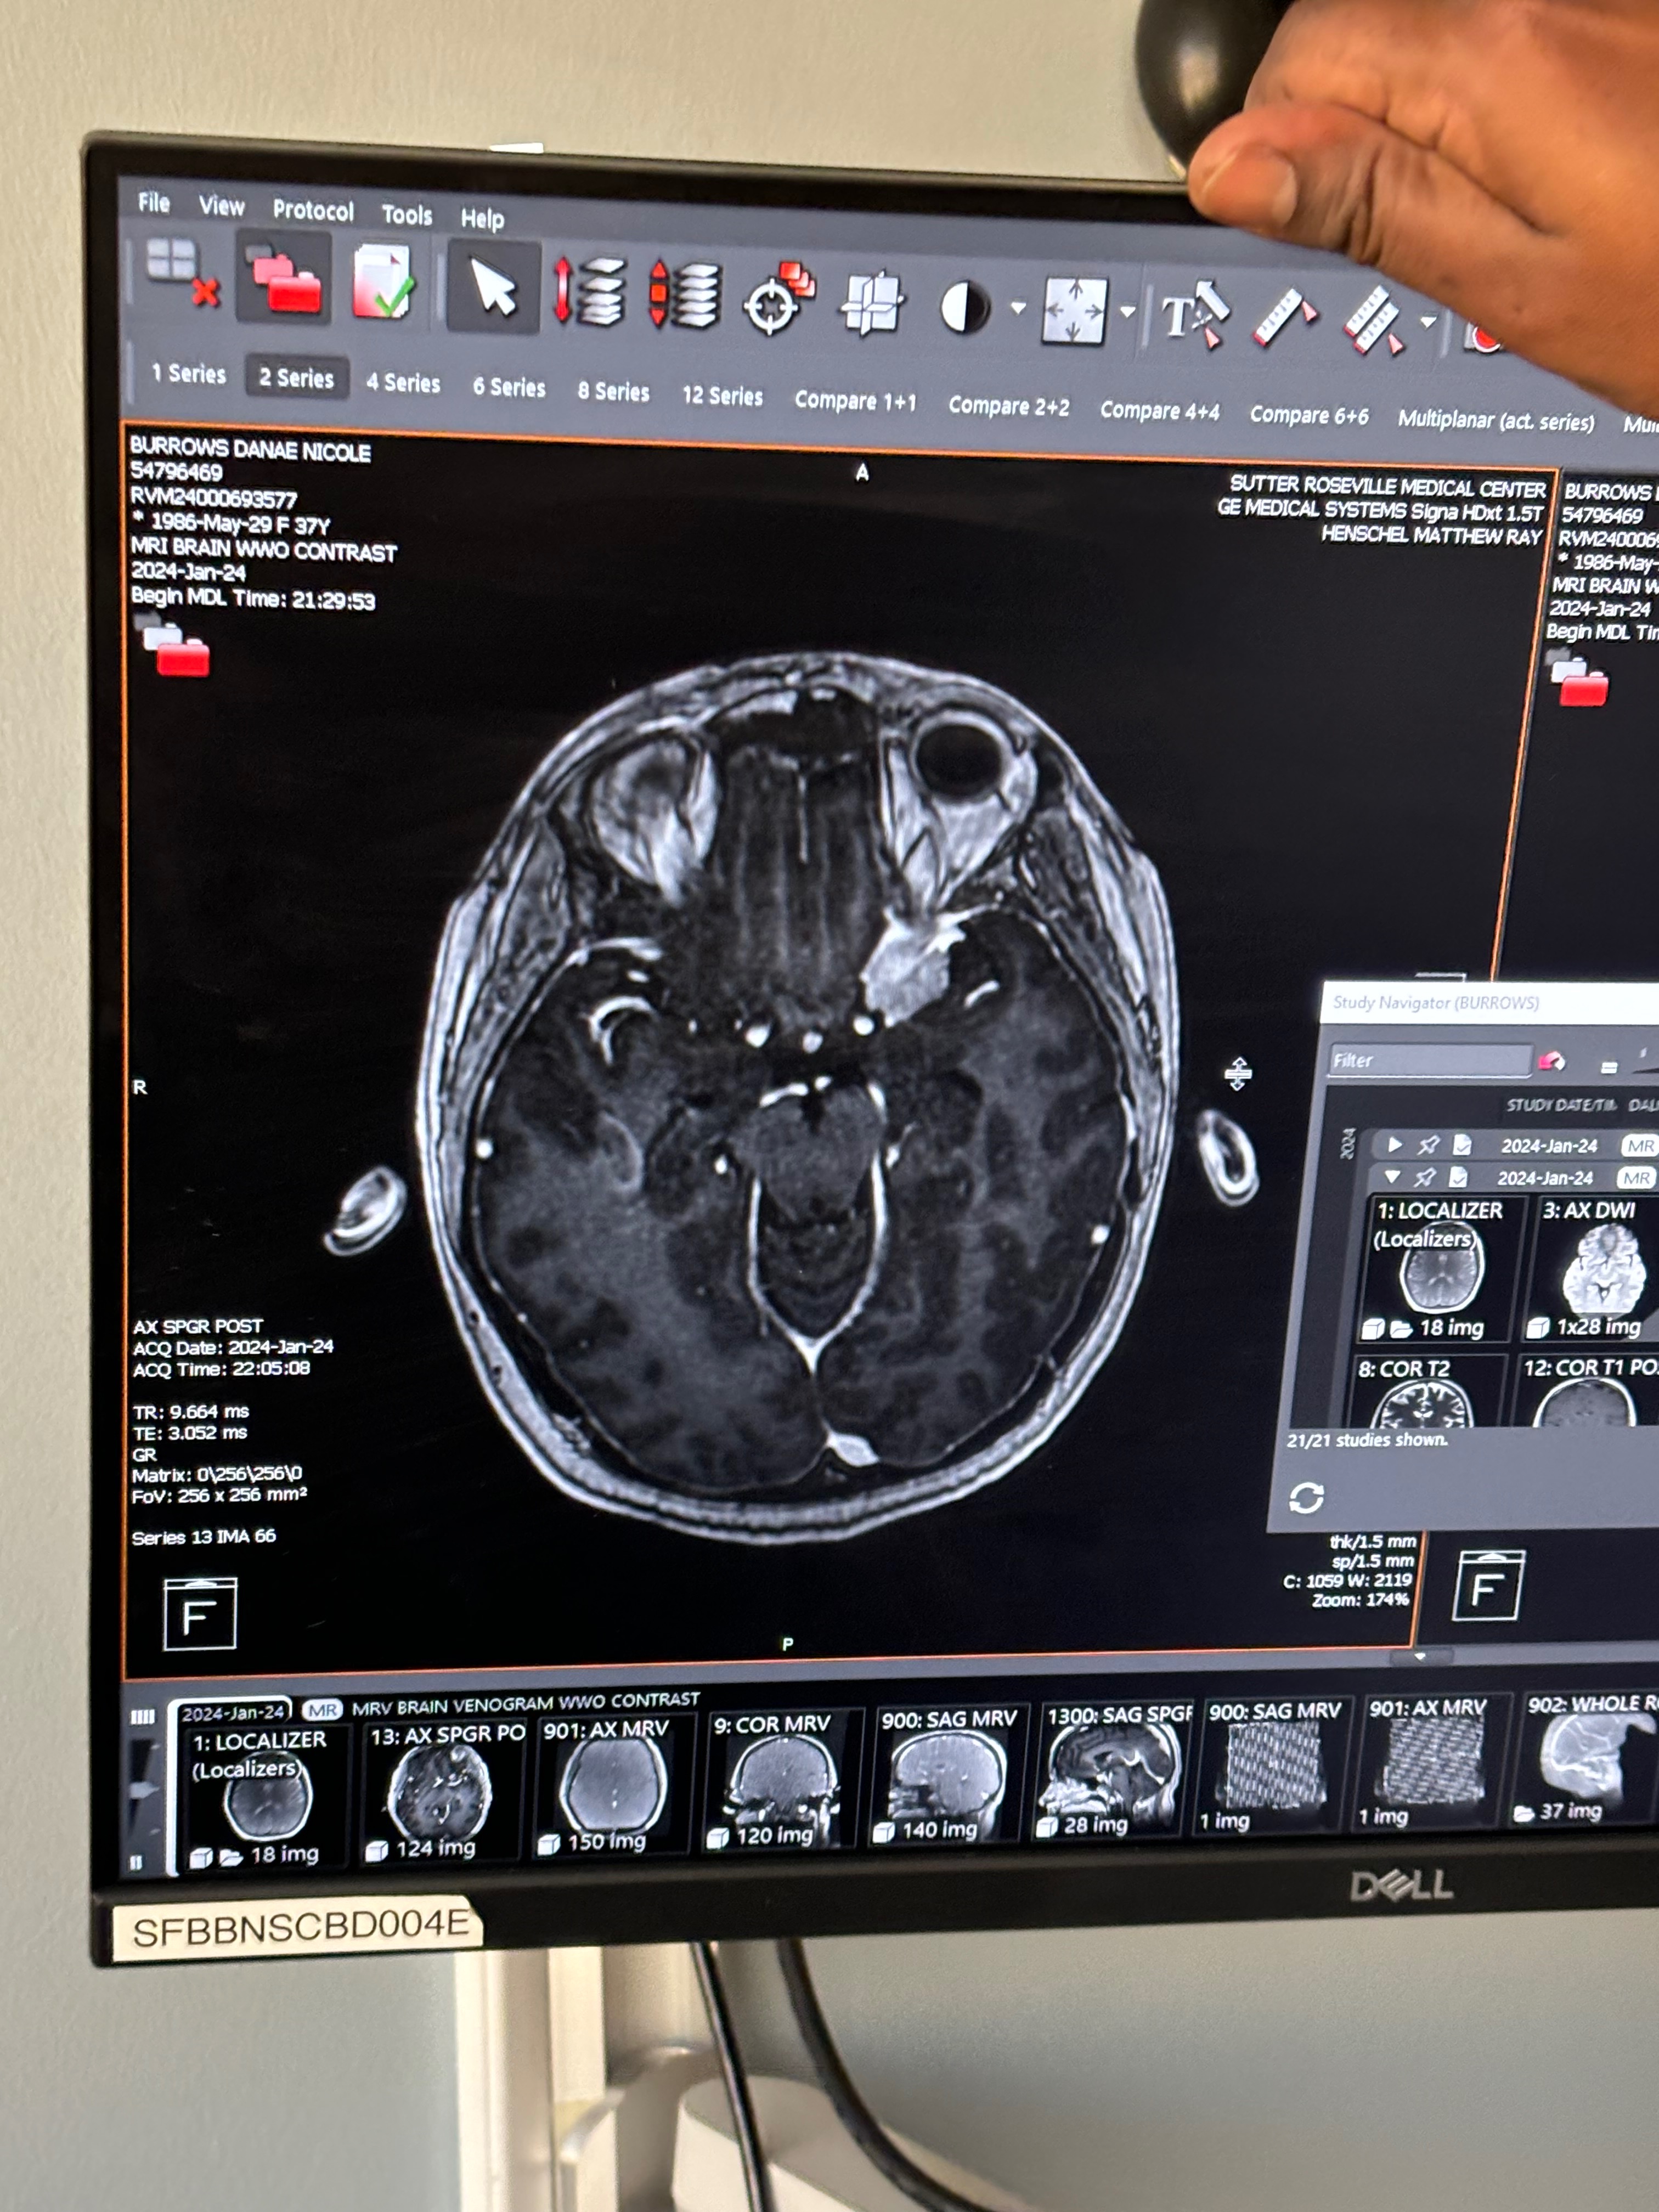

Hi, my name is Danae and I’m looking for help with funds. I recently had 2 brain surgeries to remove a tumor the was behind my left eye. Myself, friends, & family are extremely so happy I made it through both procedures. First one was 4 hours and the second one over 7 hours. I made it!